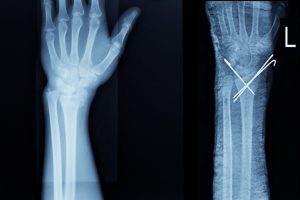

At COSM, wrist fractures are one of the most common conditions we treat, especially those involving the distal radius. Some fractures can be managed in a cast or brace, while more severe or displaced fractures often require expert surgical care.

- Recommended for displaced or unstable fractures

- Performed by our COSM orthopedic surgeons using plates, screws, or bone grafting if required

- Ensures proper alignment and long-term wrist stability